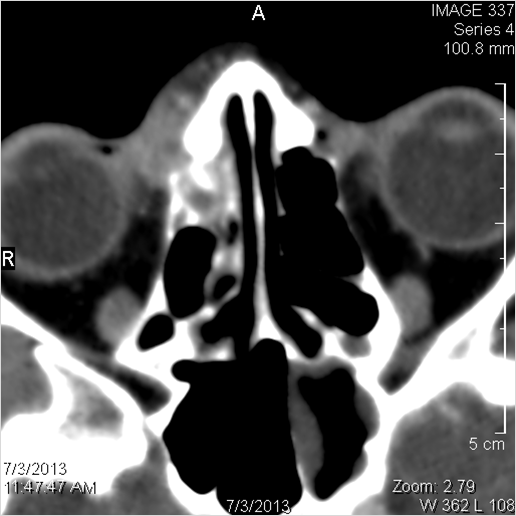

There is mucoperiosteal thickening in the sinuses.

There is a deeply infiltrating, necrotic or ulcerative process of the nasopharynx.

There is evidence of inflammatory changes within the parapharyngeal fat of the nasopharynx.